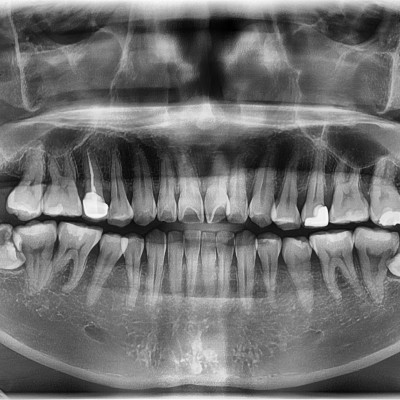

#28,38,48 사랑니 발치 #28,38,48 사랑니 발치 구강 외과 전문의가 당일 발치했습니다.